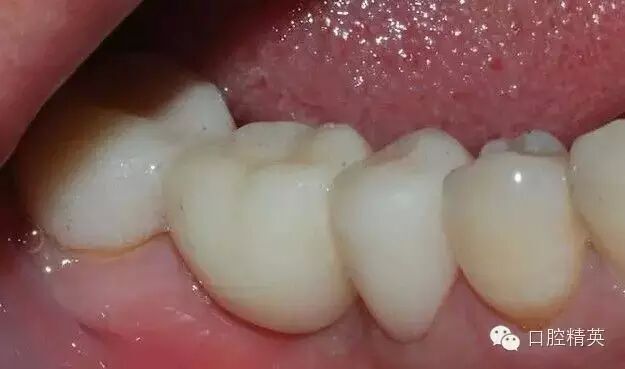

拋光后的

臨時(shí)冠

印模制取臨時(shí)冠